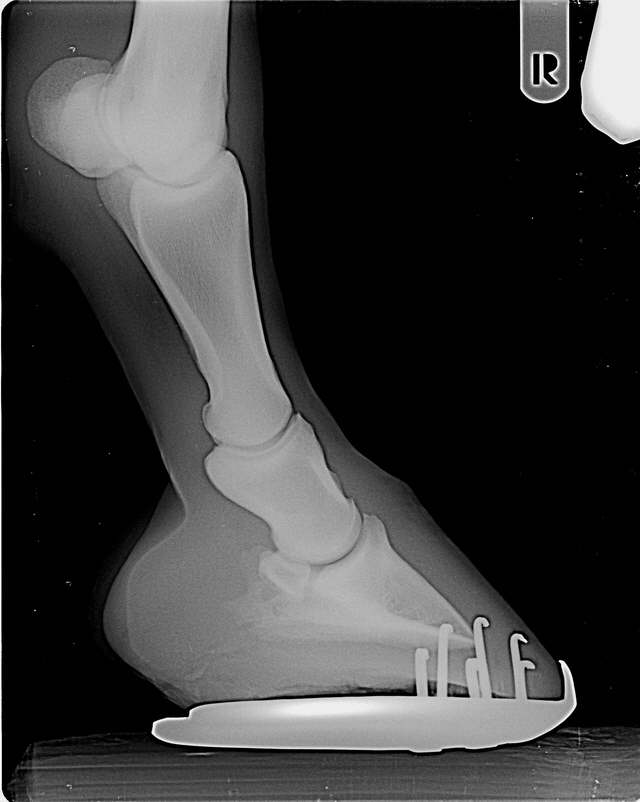

Gebrochene Zehenachse

Die Trachten beginnen flach zu werden. Frühes Stadium in dem vermutlich noch keine bleibenden Schäden vorliegen. Hier kann ein entsprechender Beschlag noch viel retten.